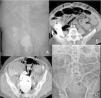

He sought medical attention at the emergency service due to inability to eat, feculent vomiting, increased abdominal perimeter, generalized colicky abdominal pain, and failure to pass gas or defecate, 4 days earlier. He was admitted to the hospital for endovenous hydration. The general laboratory work-up showed azotemia and fluid and electrolyte imbalance. Plain abdominal x-ray in two positions identified dilation of small bowel segments and the gastric chamber secondary to impaction of contrast material in the ascending colon, sigmoid colon, and rectum (Fig. 1A). An abdominal computed tomography scan revealed lower intestinal occlusion, with no evidence of a transition zone, and the presence of baroliths in the ileocecal valve and rectum (Fig. 1B and C). Manual disimpaction and oil enemas were unsuccessful due to pain and lack of cooperation. Evaluation under sedation was programmed. Fragmentation was carried out using a 25 mm Dormia basket, with the area irrigated with 2 liters of saline solution via an infusion pump. The fragments were then extracted using the basket, and the remaining residue was digitally removed, achieving total disimpaction under direct vision with flexible colonoscopy. This procedure identified stercoraceous ulcers in the rectum (Fig. 2A–D). Osmotic laxatives were administered to mobilize the barium from the ileocecal valve and facilitate its spontaneous evacuation (Fig. 1D). The patient tolerated oral diet and was discharged to his home with no complications.

Baroliths. (A) X-ray at admission showing contrast material in the ileocecal valve and rectum, along with dilation of small bowel segments and the gastric chamber. (B and C) Abdominal tomography scan showing baroliths in the ileocecal valve and rectum, with the characteristic artifact effect of barium contrast medium. (D) X-ray showing the absence of the baroliths in the colon.